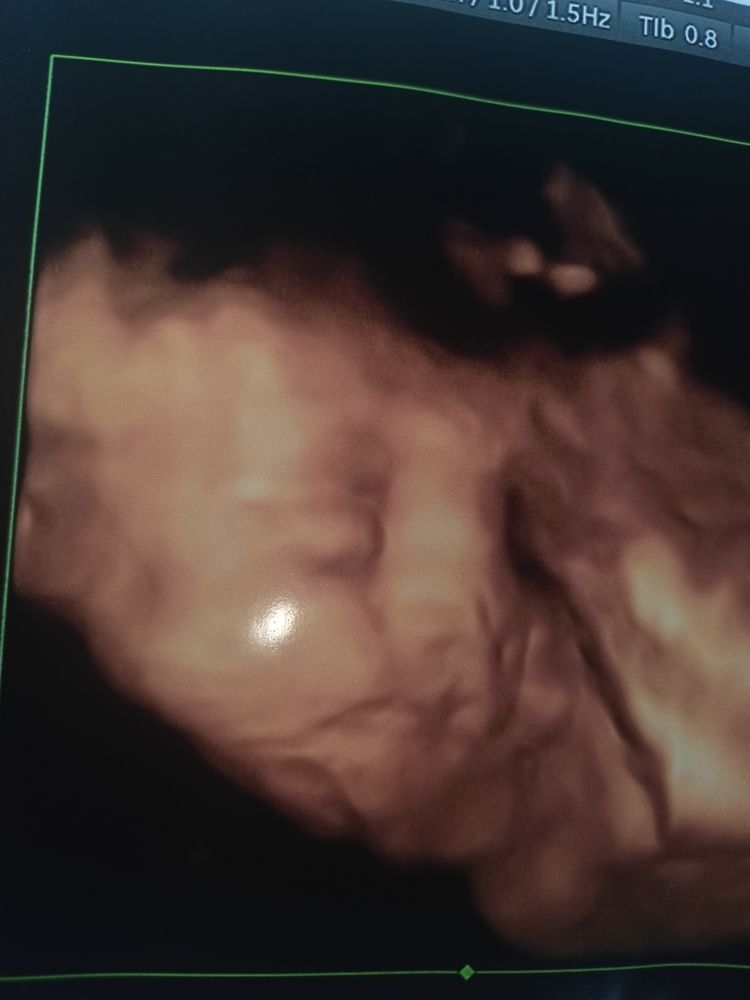

Расщелина?

Если вам узист ничего такого не сказал, то и не ищите. Красивые губки бантиком)

На снимке плохо видно. Даже если расщелина это пластика, операция делаеться в 3 месяца. Не переживай

Марина Б, Нету расщелины.

Больше похоже на просто нечеткий снимок

Просто снимок нечеткий совсем получился, обычно узисты расщелины на черно-белом уже видят

Губки это)) и тень. И щёчки ещё пупсиковые🤗 всё у вас хорошо. Не переживайте. ❤️